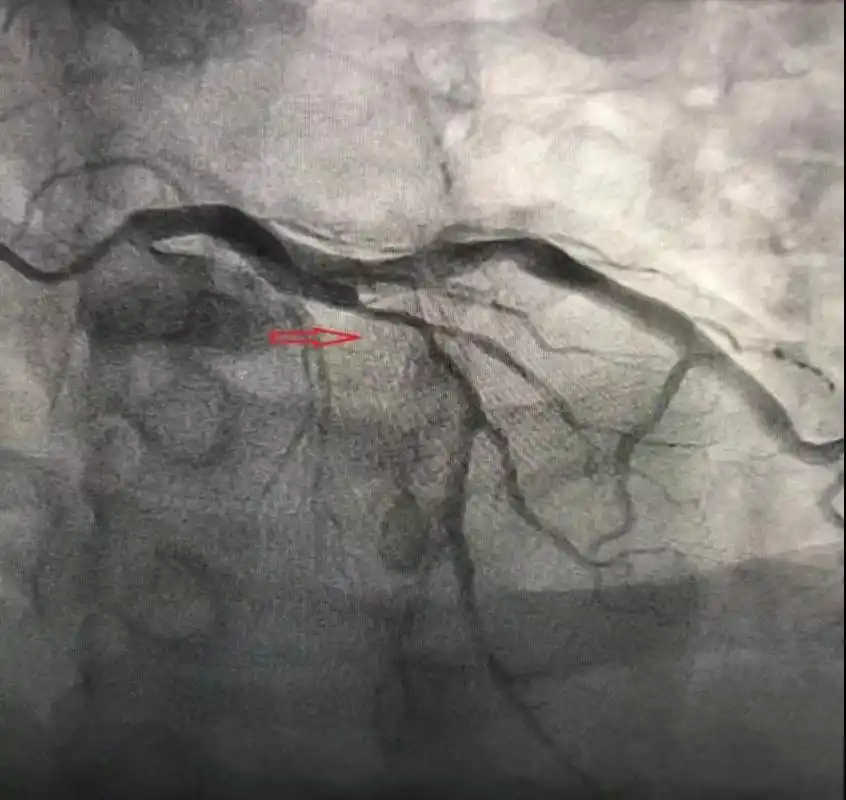

前降支近端狭窄

红色箭头处为左前降支堵塞近80%.医院 供图

一旦闭塞,死亡率高达85%以上),左前降支近中段90-95%狭窄,回旋支90%